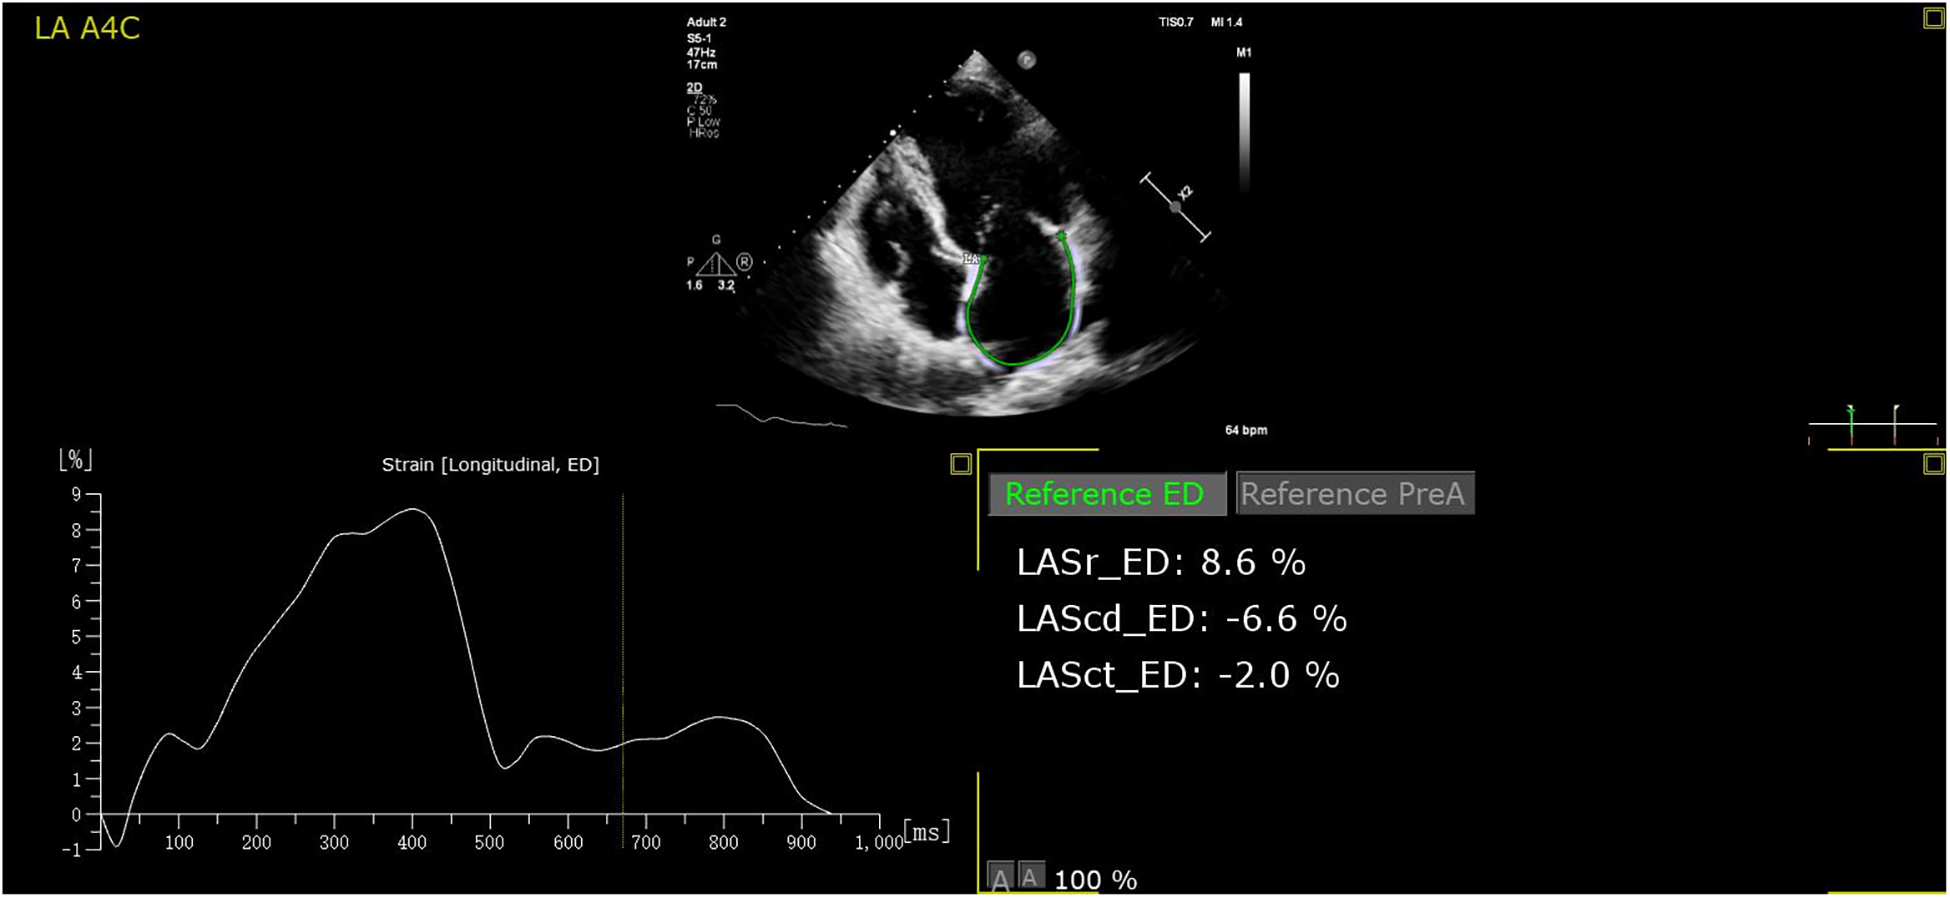

Three-heart-cycles were recorded to obtain images suitable for strain analysis. LAS analysis was performed on the Apical four- and two-chamber views with a frame rate ≥40 frames/s. Surface tracing was automatically generated by the system. Tracking was considered satisfactory if it covered the entire LA wall and with visible motion of the speckles; segments that failed to be tracked by the software were adjusted manually as required. Strain analysis was performed in all studies with adequate image quality. The automated strain detection measures LA conduit strain (LASconduit, a “positive” wave describing LA myocardial lengthening during passive conduit function); LA pump strain (LASpump, a contraction shown as a “negative” strain); and LA reservoir strain (LASreservoir, “total” strain when the LA has the maximum volume) at both end-diastole (10) (all the parameters of strain refer only to the absolute value). Offline strain analysis was performed using the Auto Strain LA algorithm (QLAB version 13.0; Philips Healthcare, Andover, MA) (Figure 2). All strain measurements were performed by two investigators. Reproducibility was assessed using a random sample of 20 patients.

Figure 2

The auto strain LA algorithm acquires the LA strain parameters at both end-diastole automatically. LASr, LASreservoir; LAScd, LASconduit; LASct, LASpump.